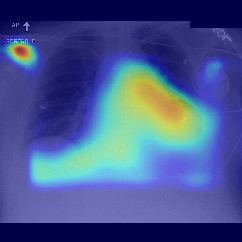

Fig.Β 5: Examples of class activation maps of positive cases. Left to right: image with annotation in blue, no L1 regularization, with L1 regularization, baseline.

Fig. 5 shows examples of class activation maps of positive cases for visual comparisons among the final models. These were produced using the Grad-CAM approach [14]. The images were annotated by an expert for the regions of opacity. Although all models correctly classified the cases as positives, the activation maps of the baseline model were barely correlated with the annotated regions, with more irrelevant hot spots outside the lungs. On the other hand, the activation maps of the models with feature selections were better correlated with the annotation. In other words, these smaller networks seems to be also more focused on the correct regions, which is a step towards explainability. The image in the third row shows that the VGG16 activation map has important components outside the lungs, focusing on English characters on the image. Whereas the reduced networks show more activation in marked areas of the lungs.